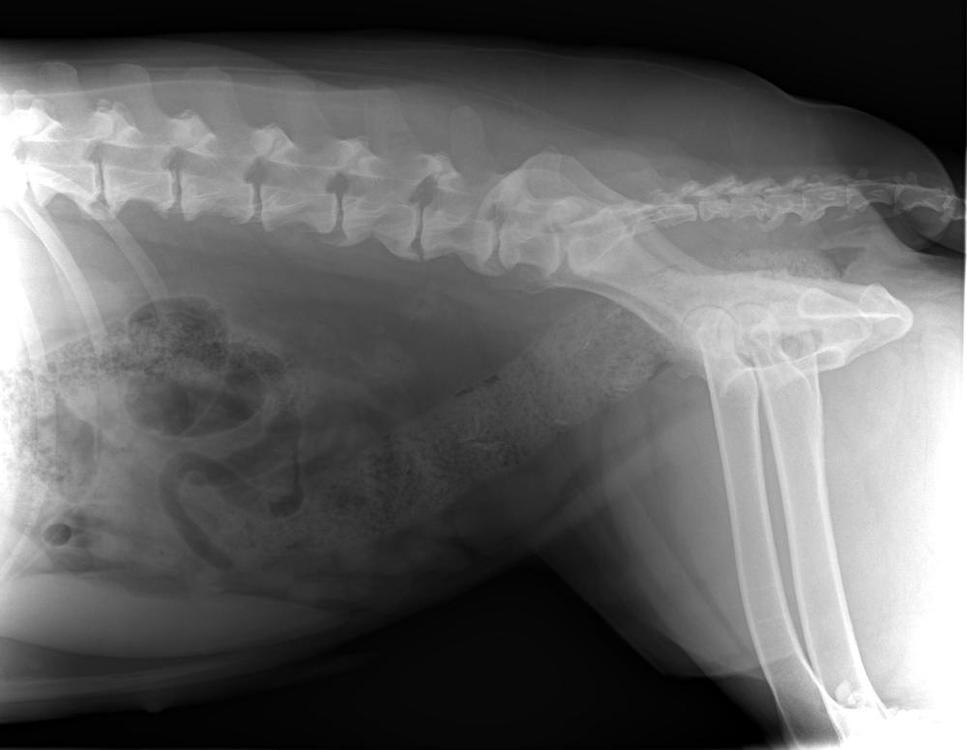

Бэкки Опубликовано 19 апреля, 2019 Опубликовано 19 апреля, 2019 Добрый день! Съездили вчера с Дусенькой к доктору, при осмотре доктор сказал, что до конца не сгибаются локтевые суставы, тазобедренные вопросов не вызвали, сделали рентген локтевых суставов и поясничного отдела. Результаты ниже. Снимки записаны на диск, но у меня нет дисковода)) Муж сможет днем на работе открыть и переслать мне, если нужны. Рекомендовано худеть и худеть на много, до 30 кг, а сейчас Дусенька 35,5 кг. , противовоспалительное пока не назначил, считает, что снижение веса значительно облегчит состояние, а пить лекарства еще успеем. Так что, будем много плавать, это нам можно, и мало кушать) 1 5